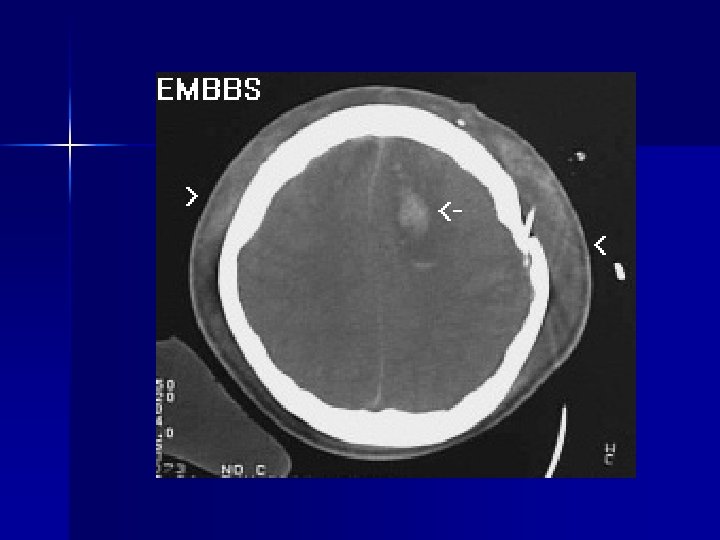

Epidural Hematoma n n n Tear in middle meningeal artery or rarely dural sinus Direct trauma with LOC, lucid interval progressing to coma Also consider if lethargy, vomiting, headache, ipsilateral dilated pupil (herniation)